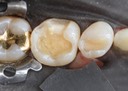

Larry Fujioka #30 caries removal